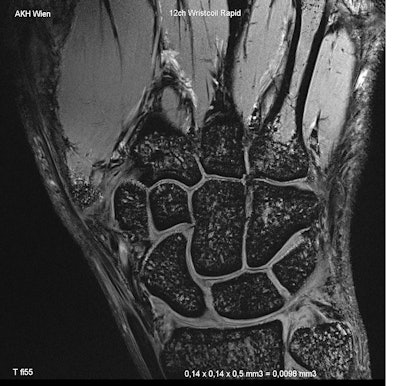

| High-resolution anatomical-morphological image of the wrist of a volunteer, during normal examination time at 7 tesla. (All images provided by Prof. Siegfried Trattnig) |